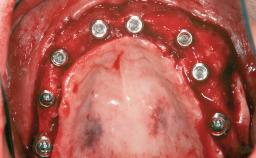

# of Implants 14

Bone Augmentation Horizontal|Sinus Floor Elevation|Staged|Vertical